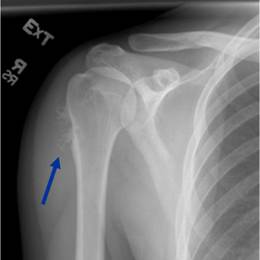

• • 50% of all cases occur in the long bone of the arm, called the humerus.

Radiographic imaging is used to help form a diagnosis. These include X-Ray, MRI, CT and Bone Scans

An example of a X-Ray is shown.